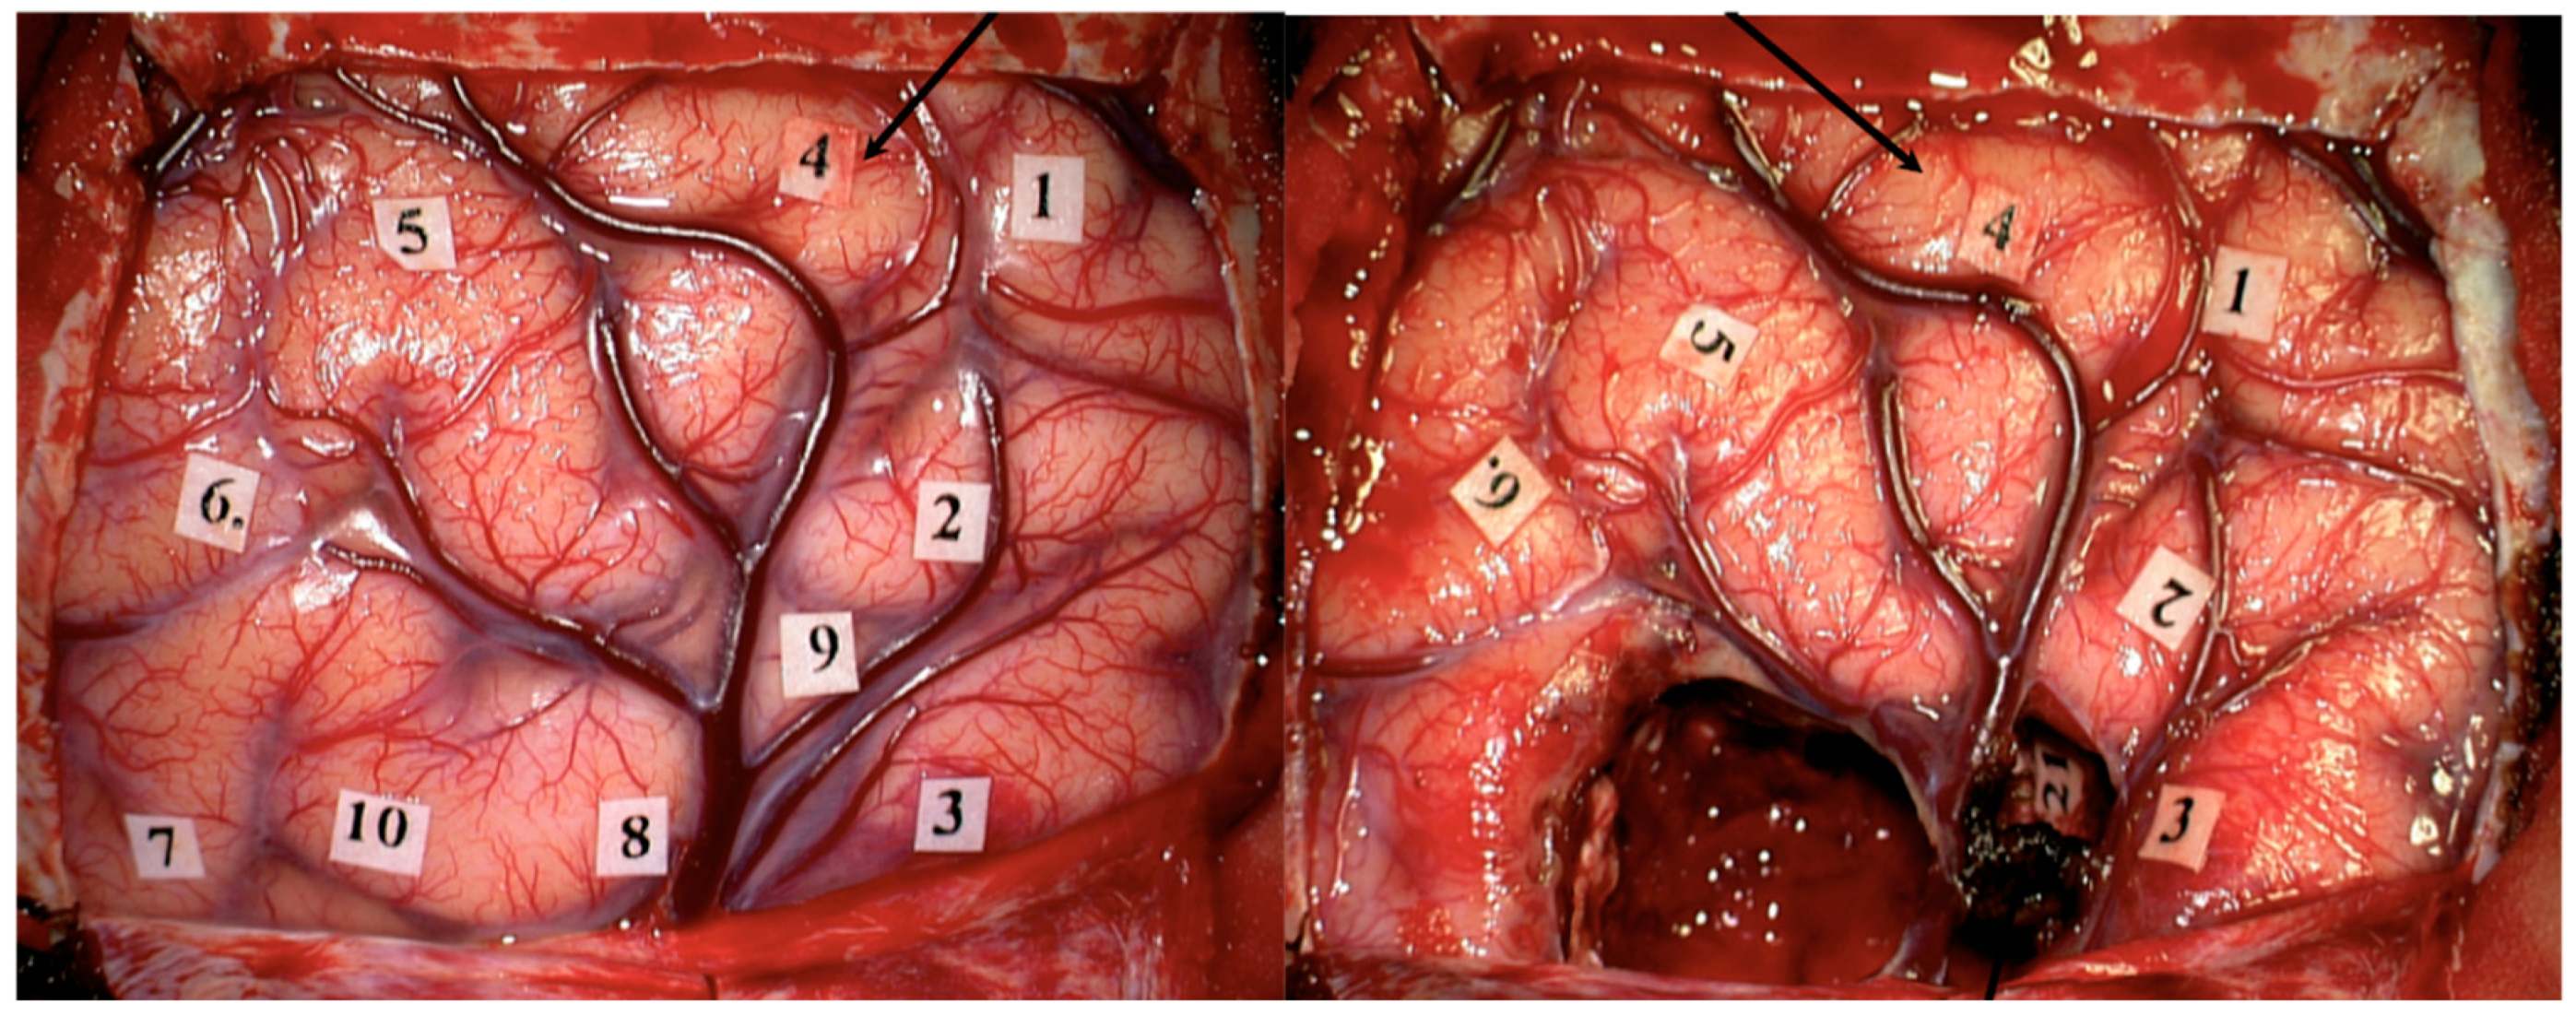

- Sanai, N.; Berger, M.S. Intraoperative stimulation techniques for functional pathway preservation and glioma resection. Neurosurg. Focus 2010, 28, E1. [Google Scholar] [CrossRef] [PubMed]

- Sanai, N.; Mirzadeh, Z.; Berger, M.S. Functional Outcome after Language Mapping for Glioma Resection. N. Engl. J. Med. 2008, 358, 18–27. [Google Scholar] [CrossRef]

- De Witt Hamer, P.C.; Robles, S.G.; Zwinderman, A.H.; Duffau, H.; Berger, M.S. Impact of Intraoperative Stimulation Brain Mapping on Glioma Surgery Outcome: A Meta-Analysis. J. Clin. Oncol. 2012, 30, 2559–2565. [Google Scholar] [CrossRef]

- Duffau, H.; Lopes, M.; Arthuis, F.; Bitar, A.; Sichez, J.-P.; Van Effenterre, R.; Capelle, L. Contribution of intraoperative electrical stimulations in surgery of low grade gliomas: A comparative study between two series without (1985–96) and with (1996–2003) functional mapping in the same institution. J. Neurol. Neurosurg. Psychiatry 2005, 76, 845–851. [Google Scholar] [CrossRef]

- Bello, L.; Riva, M.; Fava, E.; Ferpozzi, V.; Castellano, A.; Raneri, F.; Pessina, F.; Bizzi, A.; Falini, A.; Cerri, G. Tailoring neurophysiological strategies with clinical context enhances resection and safety and expands indications in gliomas involving motor pathways. Neuro-Oncology 2014, 16, 1110–1128. [Google Scholar] [CrossRef]

- Rossi, M.; Nibali, M.C.; Viganò, L.; Puglisi, G.; Howells, H.; Gay, L.; Sciortino, T.; Leonetti, A.; Riva, M.; Fornia, L.; et al. Resection of tumors within the primary motor cortex using high-frequency stimulation: Oncological and functional efficiency of this versatile approach based on clinical conditions. J. Neurosurg. 2020, 133, 642–654. [Google Scholar] [CrossRef]

- Rossi, M.; Viganò, L.; Puglisi, G.; Nibali, M.C.; Leonetti, A.; Gay, L.; Sciortino, T.; Fornia, L.; Callipo, V.; Lamperti, M.; et al. Targeting Primary Motor Cortex (M1) Functional Components in M1 Gliomas Enhances Safe Resection and Reveals M1 Plasticity Potentials. Cancers 2021, 13, 3808. [Google Scholar] [CrossRef]

- Rossi, M.; Puglisi, G.; Nibali, M.C.; Viganò, L.; Sciortino, T.; Gay, L.; Leonetti, A.; Zito, P.; Riva, M.; Bello, L. Asleep or awake motor mapping for resection of perirolandic glioma in the nondominant hemisphere? Development and validation of a multimodal score to tailor the surgical strategy. J. Neurosurg. 2022, 136, 16–29. [Google Scholar] [CrossRef]